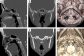

Radiological Assessment of Clival Morphological Variants in the Thai Population Using Computed Tomography